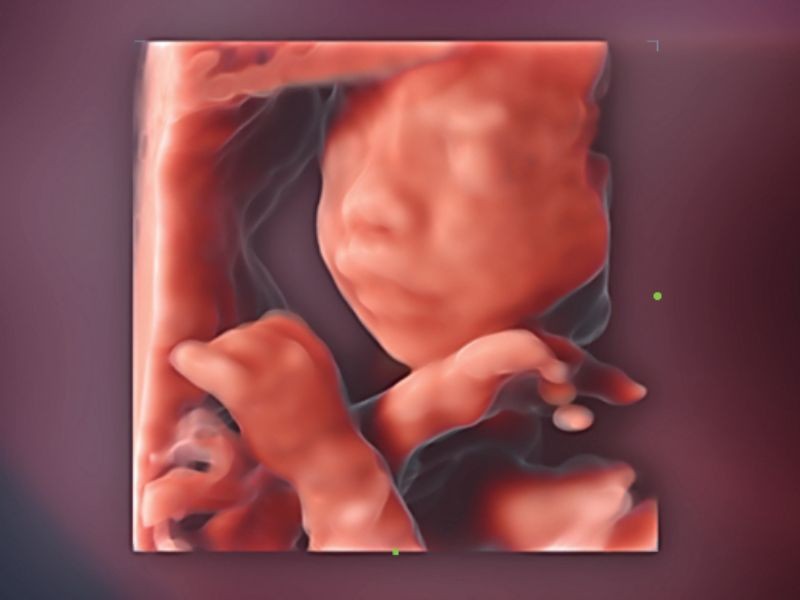

Cena Inteligente 3D

Solução obstétrica inteligente full-stack com tecnologia ZST⁺

Rosto Inteligente

Remoção automática de oclusões sobre a face fetal com um clique

OB inteligente

Medição automática de biometria fetal

Aviões inteligentes CNS

Reconhecimento automático e medição do sistema nervoso central fetal